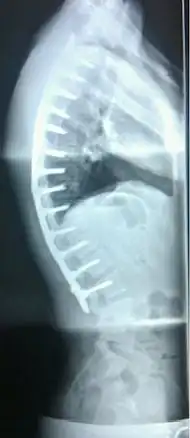

A pre-operative image of a 22-year-old male with a very extreme case of Scheuermann's disease

A post-operative X-ray of a 22-year-old male with Scheuermann's disease. After a 13-level spinal fusion to correct the excessive curvature, the person now presents a normal degree of kyphosis, with a minimal loss of flexibility.

In severe or extreme cases, patients may be treated through an extensive surgical procedure in an effort to prevent the disease from worsening or harming the body. The skeletal deformity caused by Scheuermann's disease can be corrected or partially corrected with surgical procedures, almost all of which include multi-level spinal fusion and hardware instrumentation, i.e., rods, pedicle screws, etc. It is important to realize the surgery aims to reduce pain, and not cosmetic defect. As always, surgical intervention should be used as a last resort once conservative treatment fails or the patient's health is in imminent danger as any surgical procedure is not without risk. However, the chances of complication are relatively low, and the surgeries are often successful.

There are two primary surgical techniques to correct kyphosis: posterior-only fusion and anterior/posterior fusion. While debate lingers over which surgical approach is optimal, several studies published since 2018 suggest treatment trends are favoring posterior-only fusion.[17][18][19]

The classic surgical procedure entails entering two titanium rods, each roughly 1.5 feet (0.46 m) long (depending on the size of the kyphosis) into the back on either side of the spine. Eight titanium screws and hardware are drilled through the bone to secure the rods onto either side of the spine. On the internal-facing side of the spine, ligaments (which can be too short, pulling the spine into its abnormal shape) must be surgically cut or released, not only stopping part of the cause of the kyphosis, but also allowing the titanium rods to pull the spine into a more natural position. The damaged discs between the troubled vertebrae (wedged vertebrae) are normally removed and replaced with bone grafting from the hip or other parts of the vertebrae, which once healed or "fused" will solidify. The titanium instrumentation holds everything in place during healing. The patient can expect to remain in hospital for a minimum of a week, and possibly longer. They may then be required to wear a brace for several months more to ensure the spine heals appropriately. The titanium instrumentation may stay in the body permanently, or be removed years later. Patients who have undergone such surgery may need physical therapy to manage pain and mobility. Recovery can be prolonged: typically patients are not allowed to lift anything above 5–10 pounds (2.3–4.5 kg) for 6 months to 1 year, and many are out of work for 3 to 6 months. However, once the fusion is solidified, most patients can return to their usual lifestyle within 1–2 years.